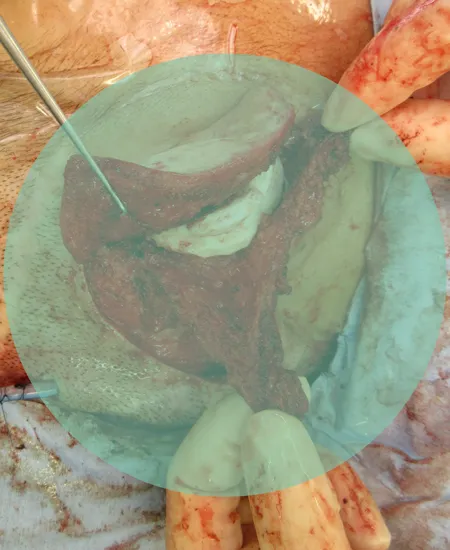

STEP 04

STEP 05

術直後の状態です。

STEP 06

耳介はしっかり立っています。